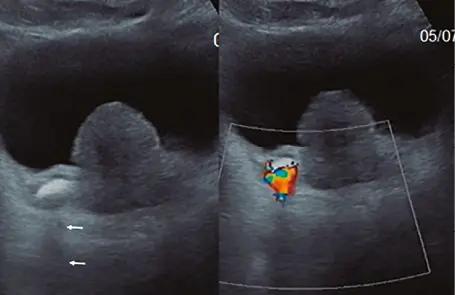

Fig: 7

Fig: 7, corte longitudinal a nivel de cabeza de epidídimo izquierdo, se puede ver: tabiques ecogénicos, regulares menores de 3. 0 mm.

Fig: 8

Fig: 8– tabique menor de 3. 0 mm, vascularizado.